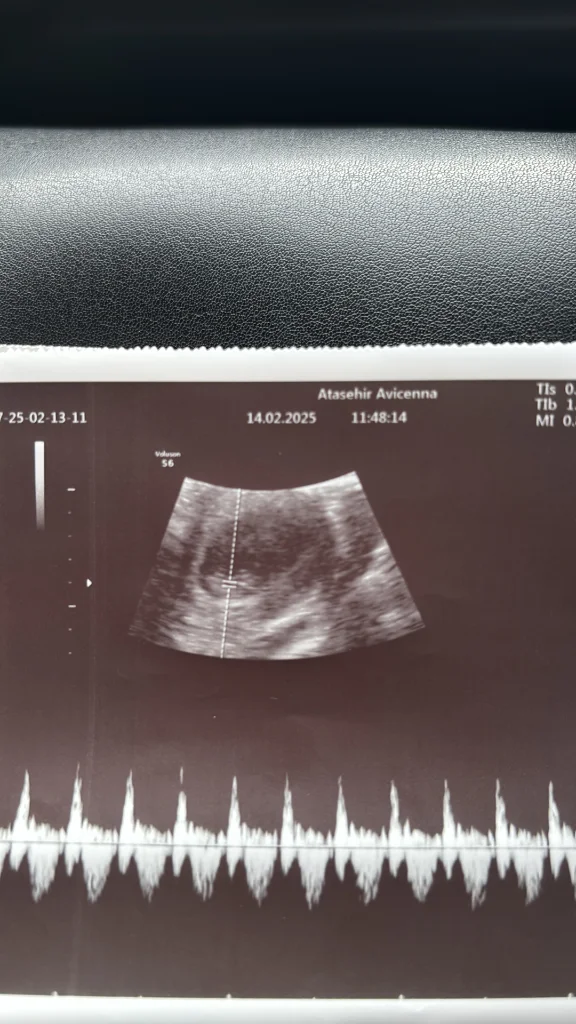

Ama kalp atış hızı erkeki gösteriyor keseyi tam çözemedim şekli beli olmamış fasulye olursa erkek yuvarlak olursü kız olur genelde

Canım buda kese tam yuvarlak değil gibi erkek hissettim kaç haftalıksın küçük gibi iki hafta geçse sanki daha iyi tahmin yapılıır sendedeEki Görüntüle 3551356 Eki Görüntüle 3551357 benimkinede bakabilir misin canım